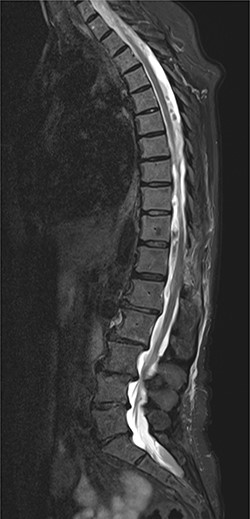

On 17 February 2020, she underwent TKA (Fig. 1). Spinal anesthesia was performed, with the patient in sitting position with one laborious puncture, as referred by the anesthesiologist. The patient received low molecular weight heparin (4000 UI enoxaparin sodium) subcutaneously 12 h after the surgery and a second shot dose 24 h later. On the second post-operative day (19 February 2020), early in the morning, the patient complained of numbness in her lower extremities and low back pain, partially relieved with analgesics. Four hours later, she was complaining for severe difficulty in moving her legs with increased low back pain. The physical examination showed flaccidly paralyzed left lower leg (0/5 left quadriceps, 0/5 left extensor digitorum longus, 0/5 left tibialis anterior and 0/5 left extensor hallucis longus), marked motor function reduction of the right lower leg (1/5 right quadriceps, 2/5 right extensor digitorum longus, 2/5 right tibialis anterior and 2/5 right extensor hallucis longus), sensory loss in both lower limbs, Babinski sign negative bilaterally and preserved sphincter functions. Magnetic resonance imaging (MRI) was required to rule out an acute spinal compression. The images showed a spindle-like mass, mostly intradural, from T11 to L3, hypointense in T2 and heterogeneous in T1 images compressing the dural sac (Fig. 2). Therefore, a diagnosis of acute spinal hematoma was made, and the patient was transferred to the Neurosurgery Department, and surgical decompression was scheduled. A bulky blood clot was removed through a spino-hemilaminectomy of T11 and T12 followed by a posterior dural incision. The source of bleeding was identified in a perimedullary vein on the dorsal surface of the spinal cord that was coagulated. Surgery was performed 3 h after diagnosis, and few hours later, the patient was able to perform a flexion-extension of both lower limbs. She was able to start walking with a walker 24 h later. A low molecular weight heparin (2000 UI Enoxaparin sodium) subcutaneously was started 1 week after surgical decompression. This dosage was increased to 4000 UI 2 days later. On 24 February 2020, a follow-up MRI was performed, and it showed a partial resolution of the hematoma with a confined area of myelopathy at the T12 level (Fig. 3). On the 26 February 2020, the patient started the rehabilitation protocol with the gradual improvement of the neurological status.

(A) The sagittal T2 FSE MRI show hypointense spindle-like mass from T10 to L3; (B) axial T1w FSE MRI showed iso-hyperintense hematoma compressing the dural sac (L1 level).